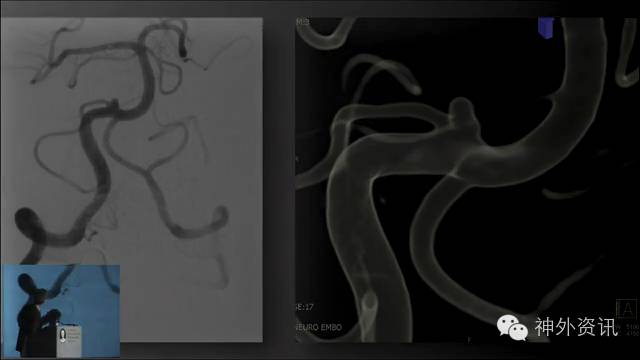

Michael T. Lawton,巴洛神经科学研究所(BNI)主席,精于各种脑血管疾病的治疗,已累及外科治疗4400余例颅内动脉瘤和700余例AVM,发表论文270余篇,参编书籍40余部,著有《Seven Aneurysms: Tenets and Techniques for Clipping》。